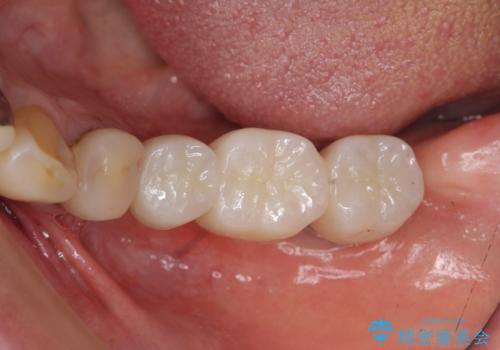

インプラントで咬合機能を取り戻す

- 左下に長年使用した入れ歯が合わず、よりしっかりと噛みたいという希望で来院されました。

入れ歯をはずししっかりと噛む手段としてインプラント治療を進めていきます。

- 90万円(ストローマンインプラント×2・チタンカスタムアバットメント×2・ジルコニアクラウン×3)費用は治療当時の料金となります

インプラントを用いることで、たくさん失ってしまった奥歯を入れ歯よりもしっかりと噛む状態へと回復することができます。